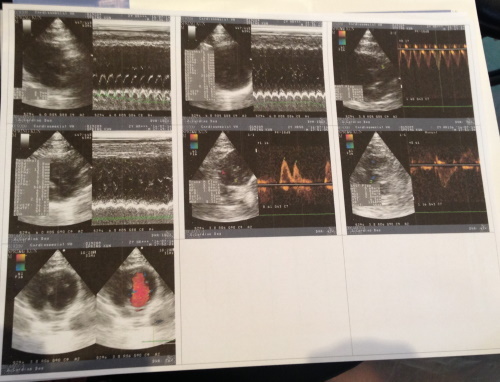

前陣子溫泉君的眼睛分泌物又開始增多,就醫檢查發現淋巴腫大,進一步抽血檢驗、超音波檢查,懷疑可能是心臟肥厚,醫師建議轉診心臟專科檢查,轉診檢查並無明顯心雜音,X光也無看出明顯異狀,心臟超音波檢查,確診溫泉君的確有心臟肥厚等問題,心臟舒張和收縮的能力較差,心臟肌肉變厚,血液進入心臟的量和壓縮量會越來越少,舉例說明,每次收縮血氧是1,因心臟肥厚每次只有0.8,若要維持100,正常需收縮100次,而心臟肥厚需收縮125次,心跳會越來越快,必須進行治療,但也有可能在治療情況下發生猝死,醫師建議要盡量讓溫泉君保持心情平穩、愉快,減少環境變動,每天按時服藥,才能夠有好的生活品質,心臟專科檢查費用還請各位幫忙。